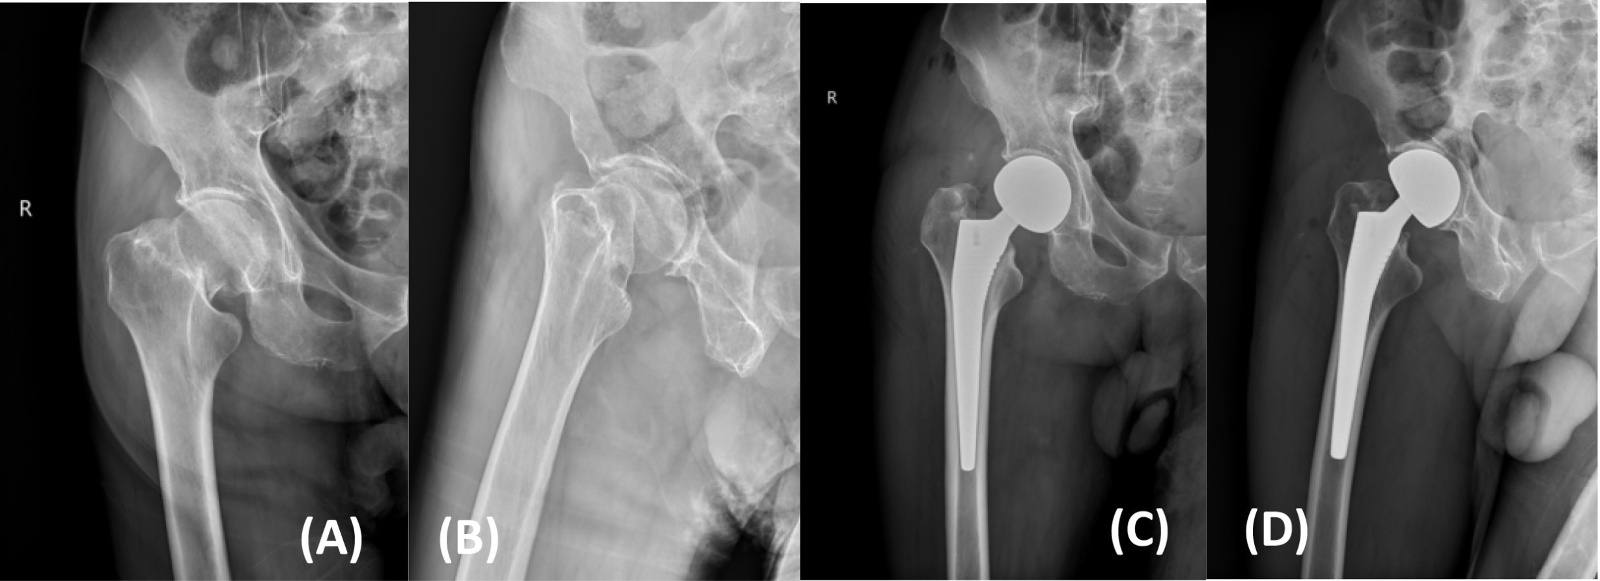

典型病例影像学表现见图1~5图1为70岁女性右侧股骨颈骨折(Garden Ⅲ型)患者,改良hardinge入路半髋关节置换术前X线示骨折断端部分错位,术后X线示假体位置良好;图2为85岁女性左侧股骨颈骨折(Garden Ⅲ型)患者,术后X线示假体位置良好;图3为83岁男性右侧股骨颈骨折(Garden Ⅲ型)患者,术后假体位置满意;图4为91岁男性左侧股骨颈骨折(Garden Ⅳ型)患者,术后假体匹配良好;图5为75岁女性左侧股骨颈骨折(Garden Ⅲ型)患者,术后假体位置正常,股骨近端微裂予钢丝捆扎固定。

Figure 3. X-ray films before and after modified hardinge approach hemiarthroplasty in an 83-year-old male patient with right femoral neck fracture (Garden type III) (A), (B). Before operation; (C), (D). After operation

3. 83岁男性右侧股骨颈骨折(Garden III型)患者改良hardinge入路半髋关节置换手术前后X线片(A)、(B) 术前;(C)、(D) 术后